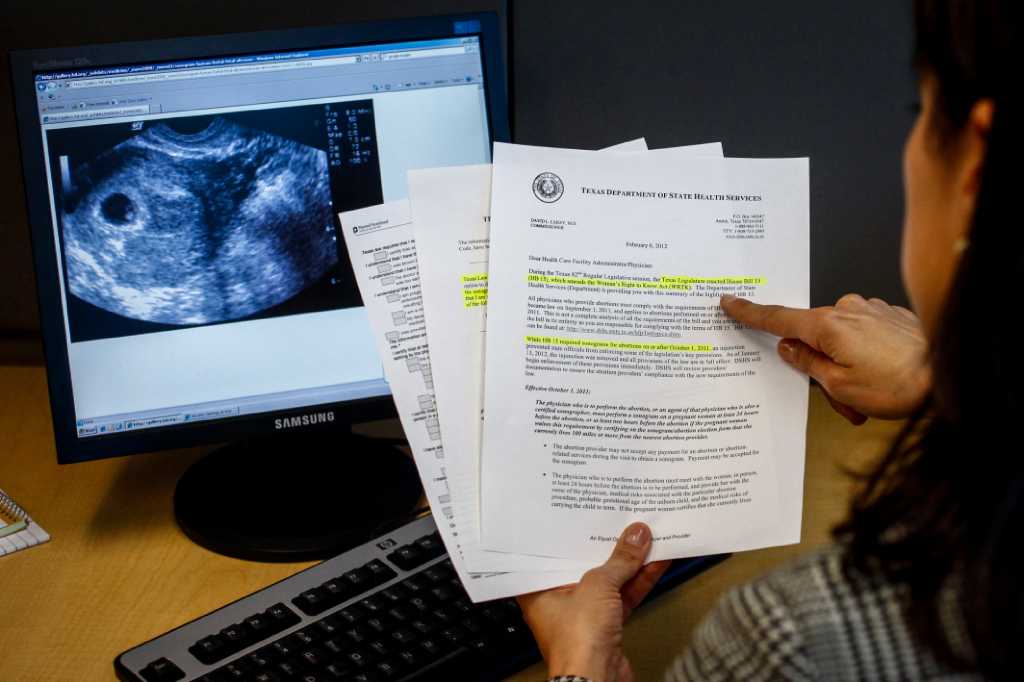

:watermark(cdn.texastribune.org/media/watermarks/2011.png,-0,30,0)/static.texastribune.org/media/images/PointingAtSonogram.jpg)